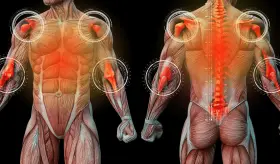

La gota es una enfermedad sistémica que puede afectar diferentes partes del cuerpo debido a la acumulación de urato monosódico en los tejidos.